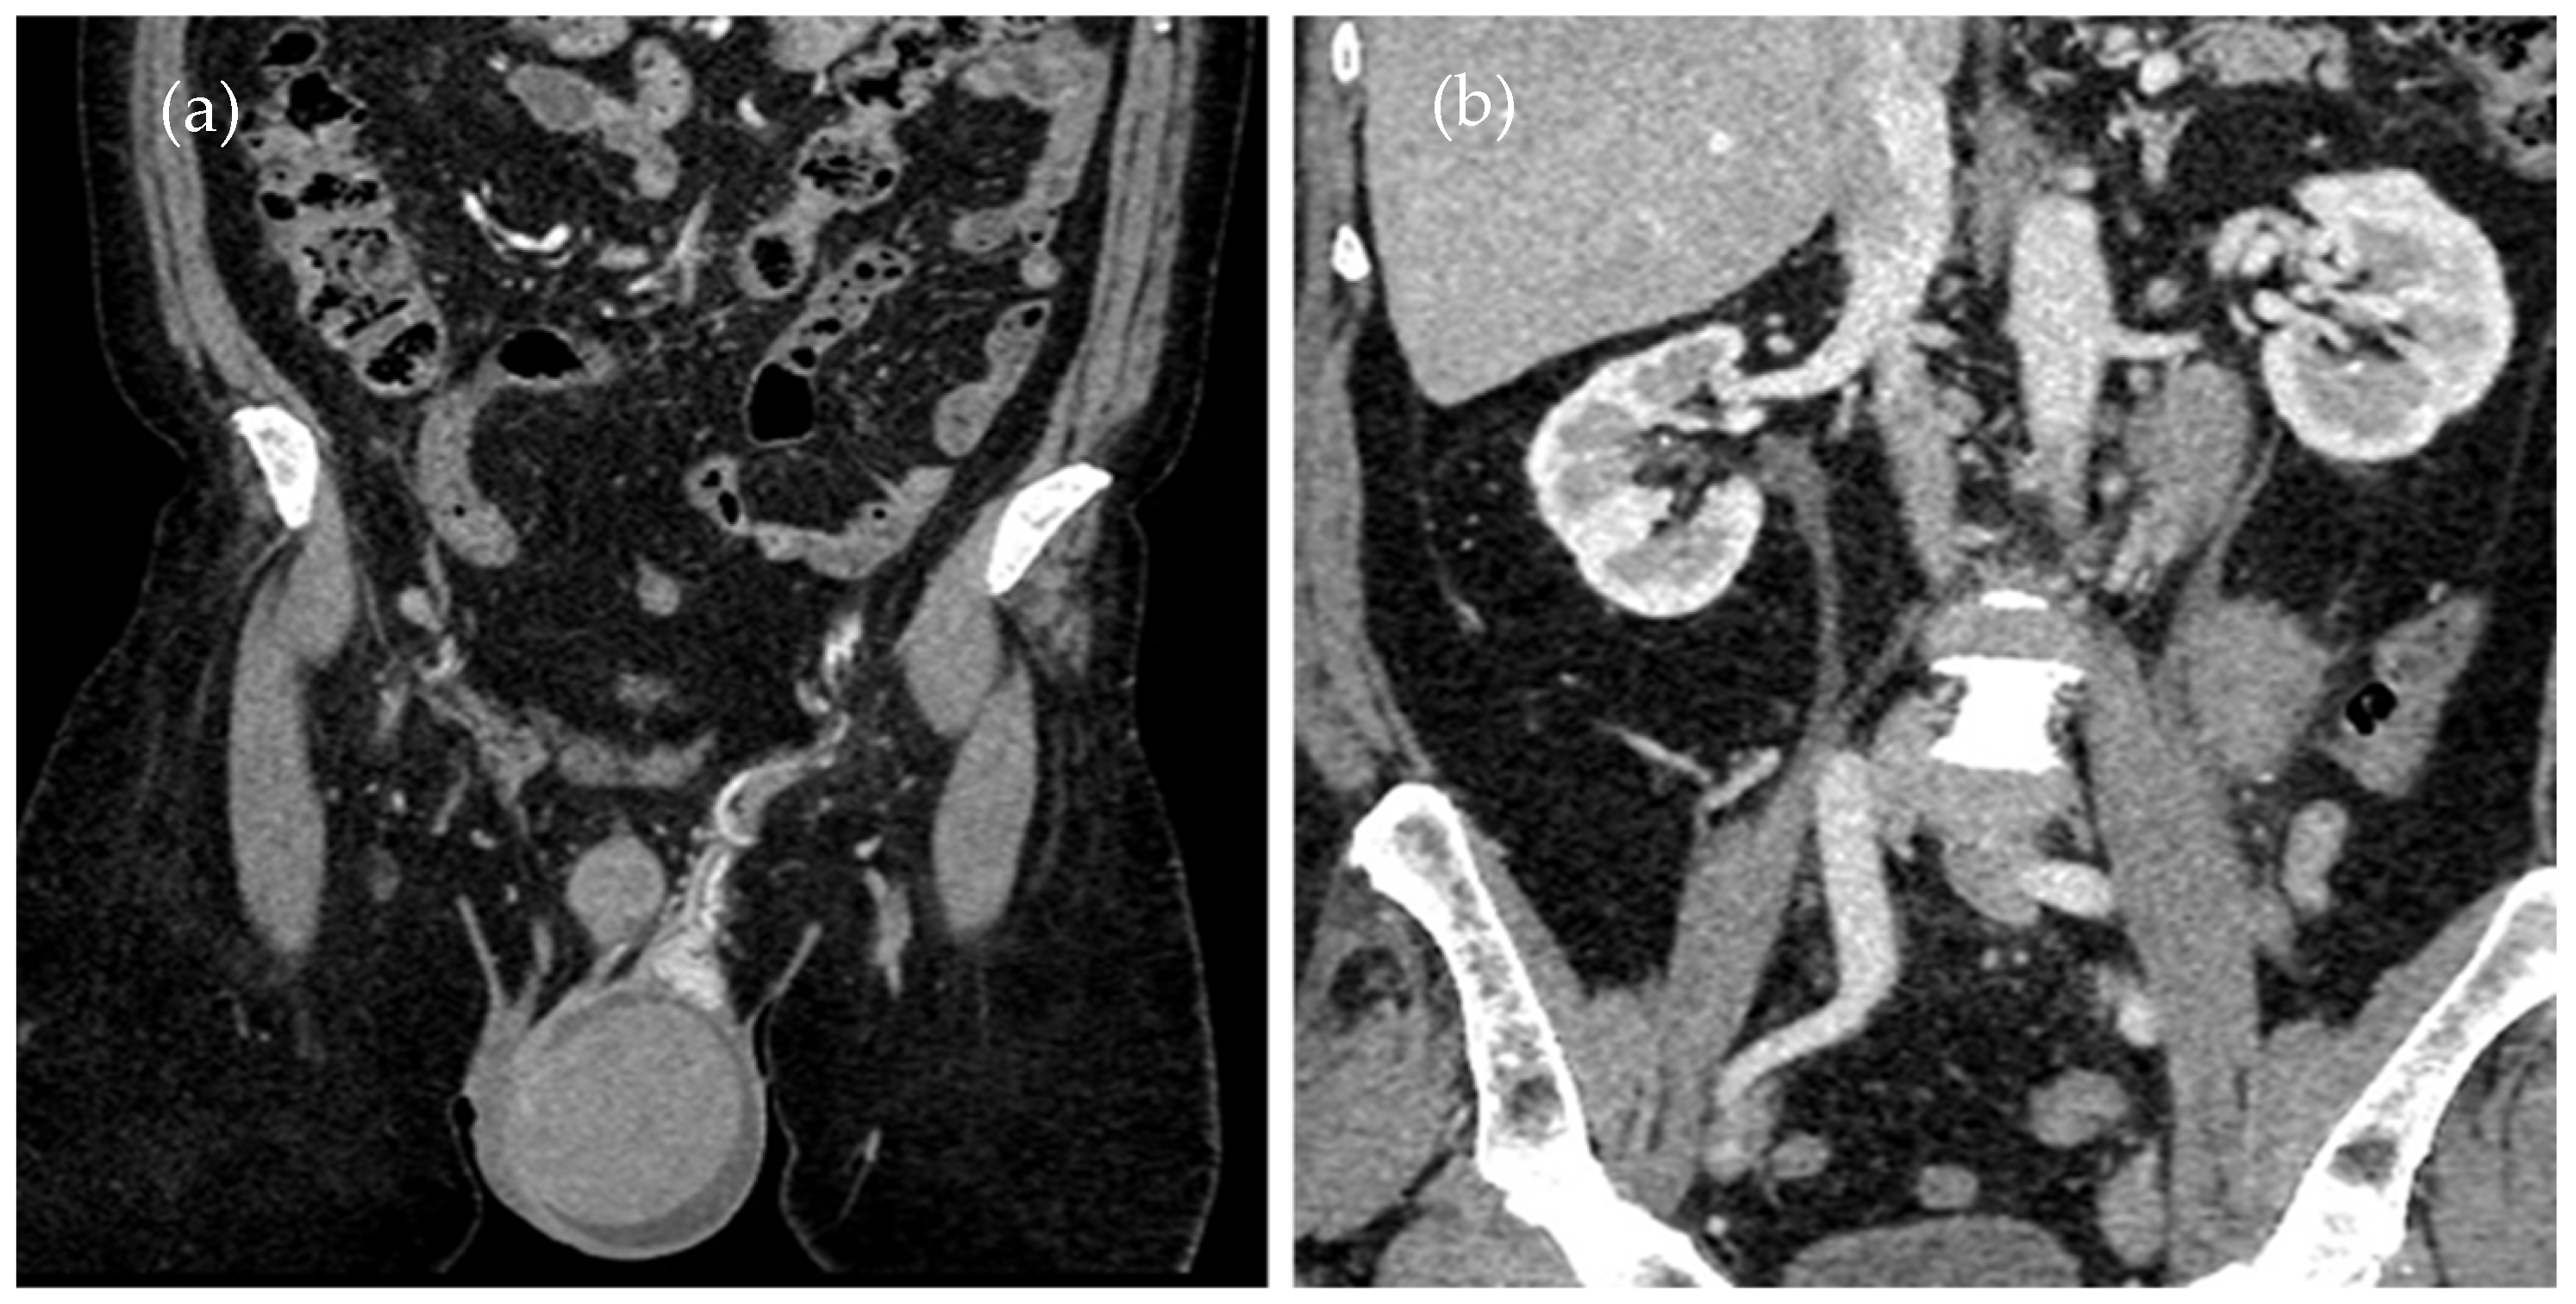

Given the history of ALL and the patient’s symptoms, a monitoring CT scan (Figure 1a,b) was performed to assess any eventual organ relapse.

A contrast-enhanced CT scan of the thorax, abdomen, and pelvis was performed, showing an enlarged left testicle (ca. 100/60/60 mm) with increased native densities (Figure 1a), rich peripheral vascularity, discreetly iodophilic in nature, with peri-testicular fluid accumulation and epididymal contrast uptake at the level of the spermatic cord and scrotum on the left, and tissular nodules with heterogeneous iodophilia along the course of the left testicular vein to the level of the left renal hilum, in keeping with adenopathy (42/26/36 mm underlying the left renal hilum, 31/27/54 mm and 13 mm, respectively Figure 1b).

Figure 1. This is a figure of abdominal–pelvic contrast-enhanced CT in the coronal plane with (a) an enlarged left testicle and (b) adenopathy on the left testicular vein pathway.